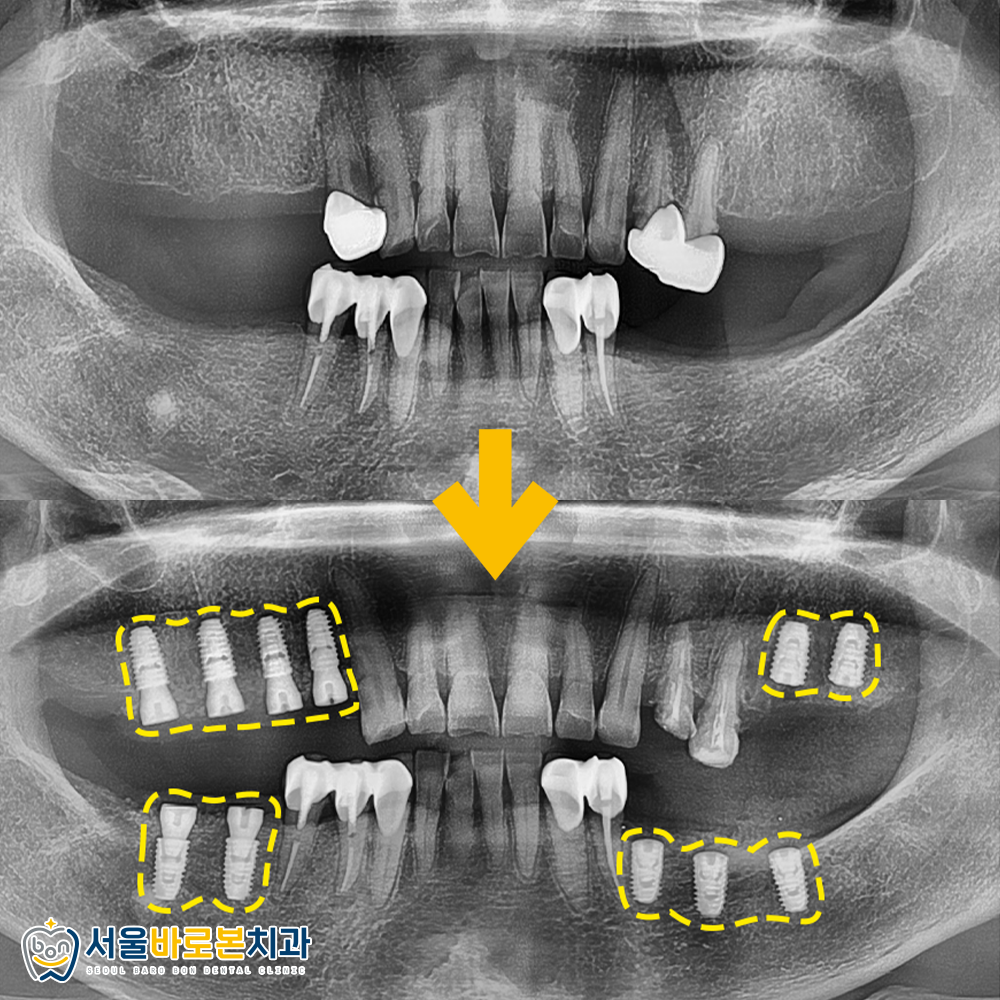

파노라마 방사선 사진상을 통해

치료 방향을 알아보겠습니다. ^^

빨간색 가위표로 표시한

작은 어금니 부위는

뿌리에 심한 충치가 있어

발치가 필요했는데요.

해당 부위와 함께

치아가 결손되어 있는 부위는

임플란트 식립을 결정했습니다.

임플란트 전후를 비교해 보았습니다.

오른쪽 위, 아래 부위 먼저 수술을 진행했는데

약 30분가량밖에 소요되지 않았는데요.

실제 입안의 오른쪽은

위의 방사선 사진상에서는

왼쪽인 점 참고 부탁드립니다!

반대쪽인 왼쪽 위, 아래 임플란트는

약 40분가량의 시간이 소요되었습니다.

골질이 오른쪽에 비해

더 약한 부위라서 10분 더 소요되었죠.